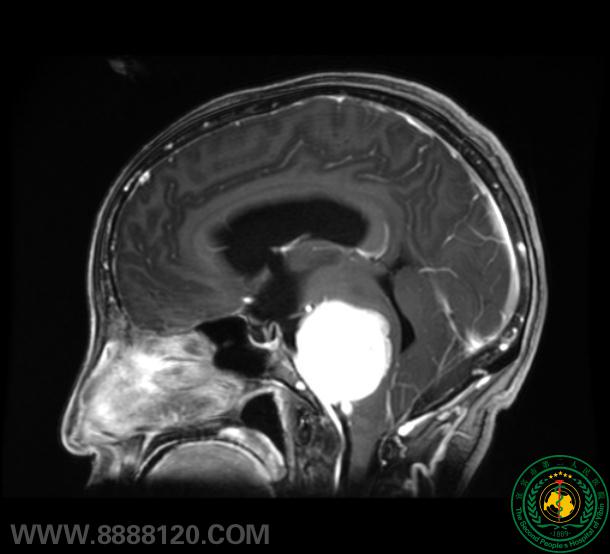

苦战7小时,宜宾市第二人民医院神外一科顺利成功切除后颅窝巨大肿瘤

苦战7小时,宜宾市第二人民医院神外一科顺利成功切除后颅窝巨大肿瘤40190